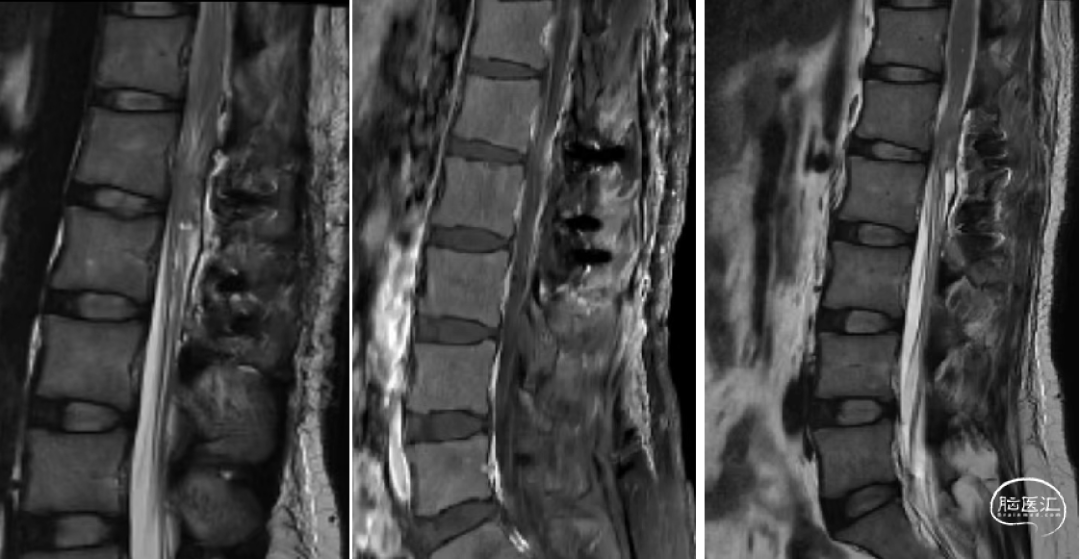

辅助检查:腰椎CT和MR示:L1-2椎管内硬膜下见一软组织信号结节,大小约24mm×12mm×10mm,T1W1低信号,T2W1稍高信号,增强扫描明显强化,但欠均匀,临近脊髓受压改变等。

术前腰椎CT和MR如下: